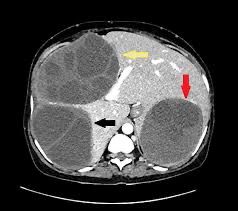

(Total Questions - 15)Q.1. Read the CT report

Correct Answer : B